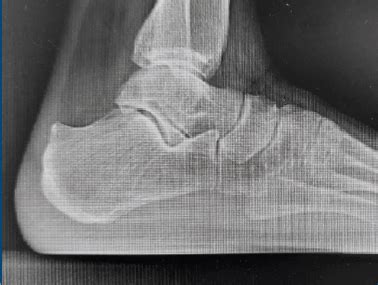

La diagnosi del Morbo di Haglund si basa su una combinazione di valutazione clinica e imaging:

- Anamnesi e Esame Clinico: Lo specialista raccoglie informazioni sulla storia del paziente, i sintomi, le attività svolte e i fattori scatenanti. Durante la visita, viene esaminato il piede, con particolare attenzione alla palpazione della zona dolente e alla valutazione dell'andatura.

- Radiografia: Le radiografie laterali del tallone sono fondamentali per confermare la diagnosi, visualizzare la protuberanza ossea, valutare eventuali calcificazioni e determinare la gravità della deformità. Tecniche come la misurazione delle linee parallele di Heneghan-Pavlov possono essere utilizzate per quantificare la prominenza.